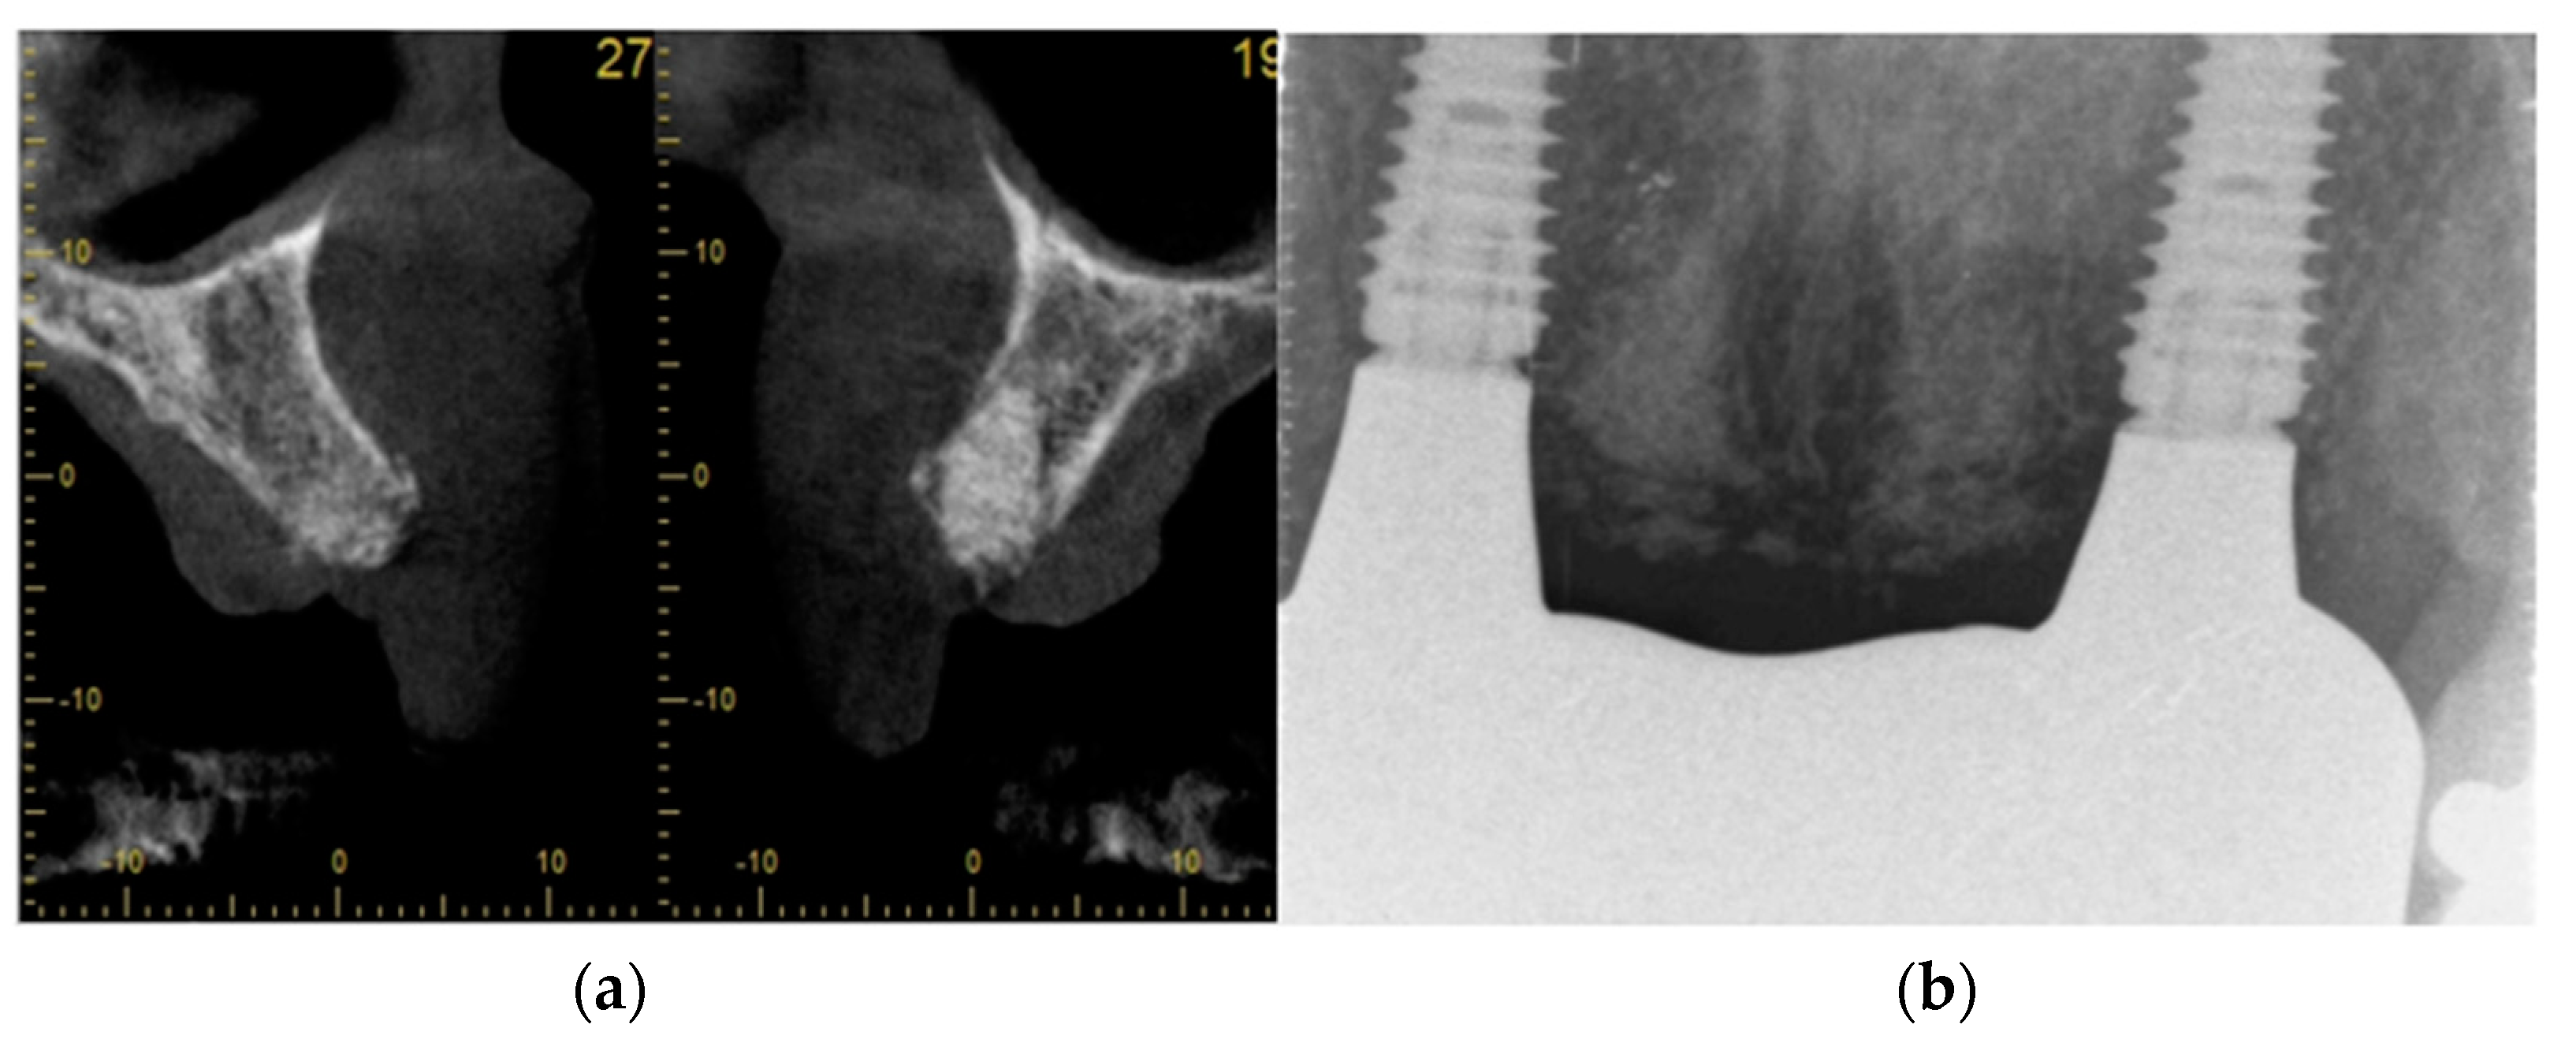

- Step 4: ARP graft healing was monitored radiologically. A CBCT was taken to plan for implant placement

- radiological assessment of bone quality and quantity after ARP using cone beam computerized tomography (CBCT)

- A CBCT scan of the sockets 8 weeks after ARP, before implant placement

| Case 1 | 60, male, prediabetes, non-smoker with no medication | open ARP | Full contour preserved | excellent | high | D2-3 | None | 8 weeks | 6 weeks | No crestal bone loss |

| Case 2 (implant 1) | 55, female, hay fever, non-smoker | open ARP | Full contour preserved | excellent | high | D2-4 | None | 9 weeks | 7 weeks | No crestal bone loss |

| Case 2 (implant 2) | 55, female, hay fever, non-smoker | open ARP | Full contour preserved | excellent | high | D2-4 | None | 9 weeks | 8 weeks | No crestal bone loss |